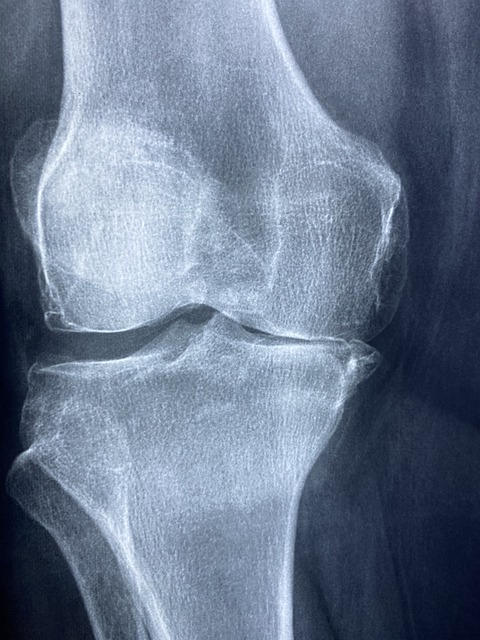

무릎 인공관절 수술은 퇴행성 관절염이나 심각한 관절 손상을 겪는 환자들에게 효과적인 치료법입니다.

무릎 인공관절 수술 후에는 합병증이 발생할 수 있습니다. 대표적인 합병증으로는 감염, 인공관절의 느슨해짐, 혈전 등이 있으며, 이로 인해 무릎 인공관절 수술 회복 기간이 길어질 수 있습니다.

합병증을 예방하기 위해서는 수술 후 초기부터 철저한 위생 관리와 정기적인 검진이 필수적입니다.